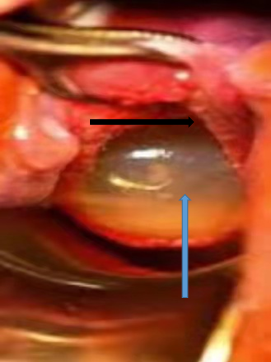

Chinese female 33 years old, G1P0, 23weeks 6days gestation age by scan, referred from a local hospital due to cervical insufficiency with cervical length of 0.309cm discovered during routine antenatal visit. (Figure 1) She presented to our hospital with complaint of lower abdominal pain which started 5 hours prior to presentation. She denied any history of vaginal bleeding, vaginal draining or discharge. Patient also denied any history of fever, headache, dizziness, cough or diarrhea. Married, other history was not significant for any risk of cervical incompetence. On physical examination, significant findings were noted on vaginal and speculum examination with open cervix of 5cm and unruptured membranes bulging through the cervical os (Figure 2).  An impression of inevitable abortion secondary to cervical insufficiency was made. Plan of emergency transvaginal cerclage placement, tocolysis/fetal protection with magnesium sulphate, oral progesterone, IV fluids for hydration, antibiotics for infection prevention and patient counselling was initiated within 1 hour after admission. The Shirodkar procedure was successfully performed without any complications after reducing the amniotic sac membranes back into the uterus (Figure 3).

Figure 2 Showing the opened cervix and bulging amniotic sac membranes.

Black arrow-cervix edge, Blue arrow-bulging amniotic membrane.